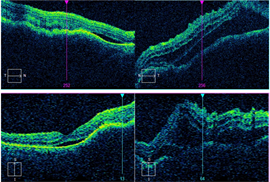

Spectral-domain optical coherence tomography (OCT) showed choroidal elevations with subretinal fluid OD and large choroidal elevation with intraretinal and subretinal fluid OS (Figure 2). Fluorescein angiography (FA) demonstrated two circumscribed areas of punctate hyperfluorescent spots located just above the superior arcade and nasal to the nerve OD and a large circumscribed area of punctate hyperfluorescent spots in the macula with central hypofluorescence OS (Figure 3). A/B scan ultrasonography shows two distinct choroidal hyperechoic lesions with high internal reflectivity in OD with maximal height of 2.90 mm and 2.50 mm and a choroidal hyperechoic lesion with high internal reflectivity with maximal height of 2.97 mm and associated subretinal fluid (Figure 4).

| Figure 1 | Figure 2 |

| Figure 3 | Figure 4 |